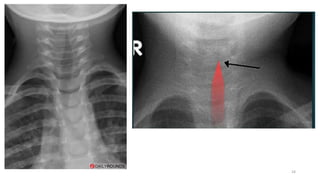

Imaging

• Radiographic confirmation is not required

• Indication:

• If the diagnosis is in question,

• Atypical course

• an inhaled or swallowed foreign body is suspected

• croup is recurrent,

• there is a failure to respond as expected to therapeutic interventions.

• Findings

• In children with croup, a posterior-anterior chest radiograph demonstrates subglottic

narrowing, commonly called the "steeple sign"

• The lateral view may demonstrate overdistention of the hypopharynx during

inspiration and subglottic haziness